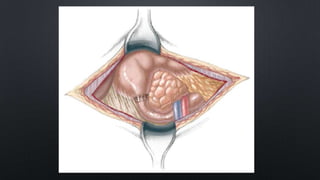

• FOR THE OPEN APPROACH  RIGHT UPPER QUADRANT SUPRAUMBILICAL TRANSVERSE

INCISION IS MADE

• AFTER MOBILIZING THE ASCENDING AND TRANSVERSE COLONS TO THE LEFT, THE

DUODENAL OBSTRUCTION IS READILY EXPOSED

CON’T • LONG SIDE-TO-SIDEDUODENODUODENOSTOMY, ALTHOUGH EFFECTIVE, IS ASSOCIATED WITH A HIGH INCIDENCE OF ANASTOMOTIC DYSFUNCTION AND PROLONGED OBSTRUCTION • DUODENOJEJUNOSTOMY  BLIND-LOOP SYNDROME APPEARS TO BE MORE COMMON • GASTROJEJUNOSTOMY  HIGH INCIDENCE OF MARGINAL ULCERATION AND BLEEDING • FOR THE OPEN APPROACH  RIGHT UPPER QUADRANT SUPRAUMBILICAL TRANSVERSE INCISION IS MADE • AFTER MOBILIZING THE ASCENDING AND TRANSVERSE COLONS TO THE LEFT, THE DUODENAL OBSTRUCTION IS READILY EXPOSED

CONT’D • MALROTATION SHOULDBE EVALUATED BECAUSE IT CAN OCCUR IN ASSOCIATION WITH CONGENITAL DUODENAL OBSTRUCTION IN UP TO 30% OF PATIENTS • A SUFFICIENT LENGTH OF DUODENUM DISTAL TO THE ATRESIA IS MOBILIZED TO ALLOW FOR A TENSION- FREE ANASTOMOSIS • A TRANSVERSE DUODENOTOMY IS MADE IN THE ANTERIOR WALL OF THE DISTAL PORTION OF THE DILATED PROXIMAL DUODENUM • A DUODENOTOMY OF SIMILAR LENGTH IS MADE IN A VERTICAL ORIENTATION ON THE ANTIMESENTERIC BORDER OF THE DISTAL DUODENUM